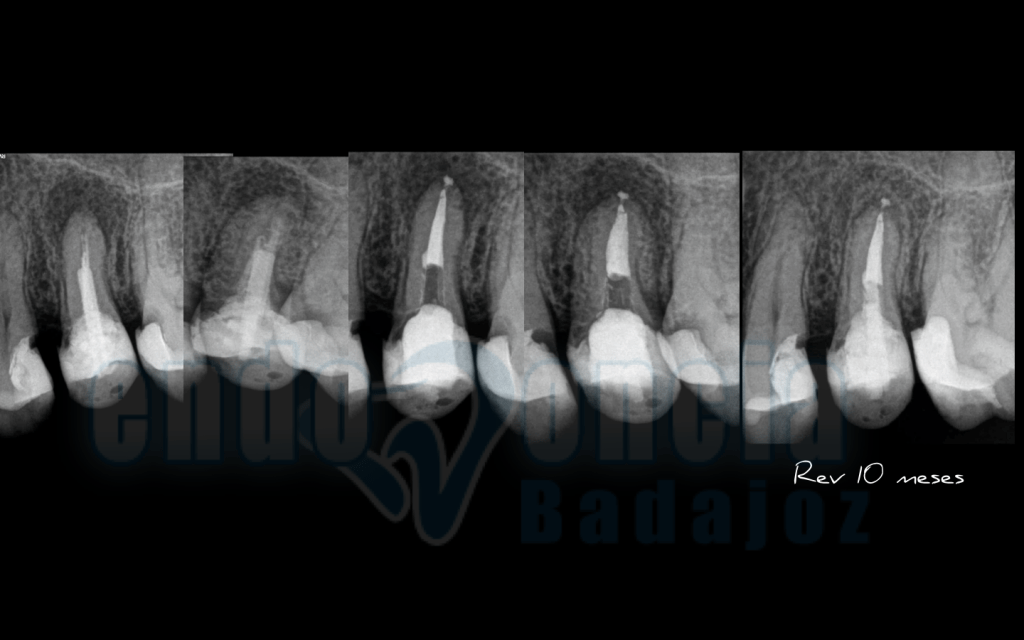

Caso 2:

Premolar superior, con un tratamiento endodóntico con perno y suboturación que presentaba una lesión apical. Retratamos la pieza y vemos como a los 10 meses existe una buena regeneración apical.